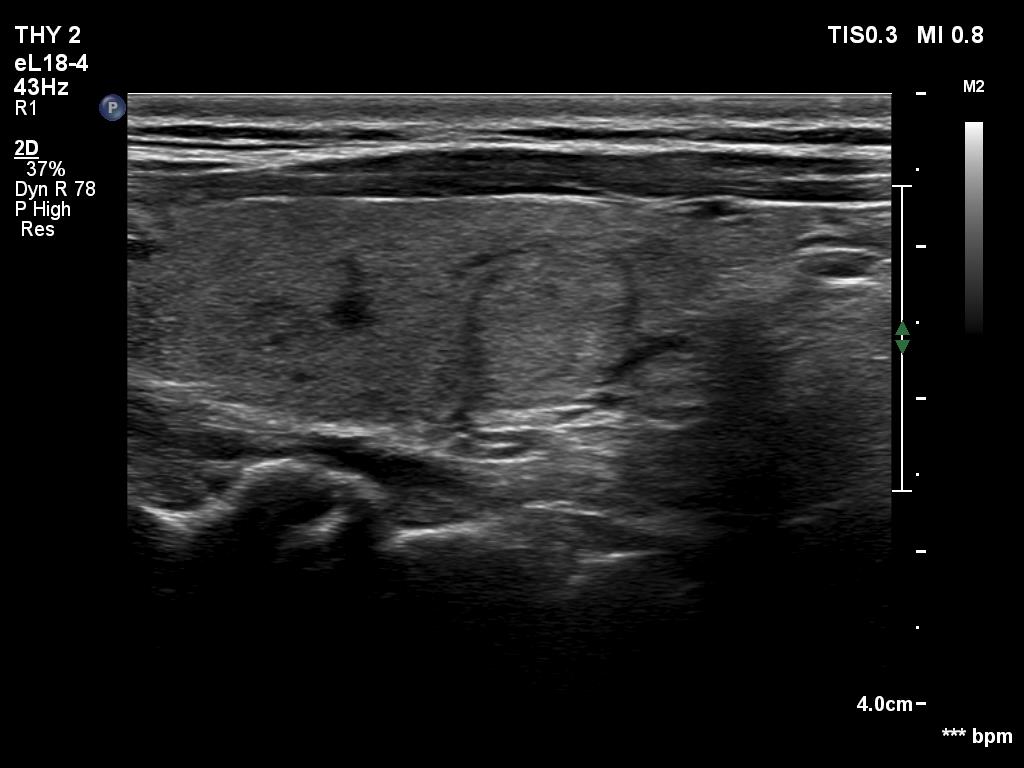

Ultrasonography. The thyroid was echonormal or minimally hypoechogenic. There was an iso/hyperechoic nodule in the right lobe. The lesion had halo and sowed taller-than-wide shape. The vascularity was not specific.

Comments. The nodule is an EU-TIRADS 5 lesion due to the nonparallel orientation.